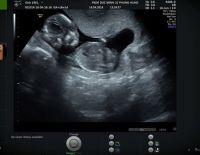

Siêu âm thai 11 tuần 6 ngày – cột mốc mẹ cần nhớ

Siêu âm thai 11 tuần 6 ngày là cột mốc đặc biệt vì đây là những tuần cuối cùng của tam cá nguyệt thứ nhất. Lúc này, thai nhi bắt đầu có sự phát triển rõ ràng hơn, nhất là hệ thần kinh, những phản...